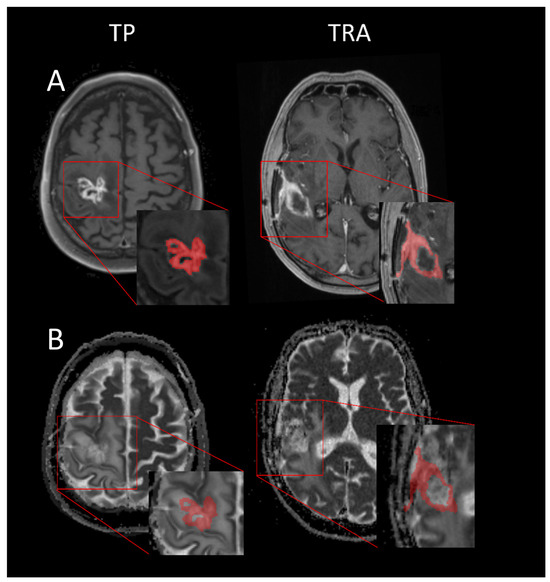

2.2. Obtaining and Analyzing the ADC Values

3.2. Comparison of ADC Values in TP and TRA